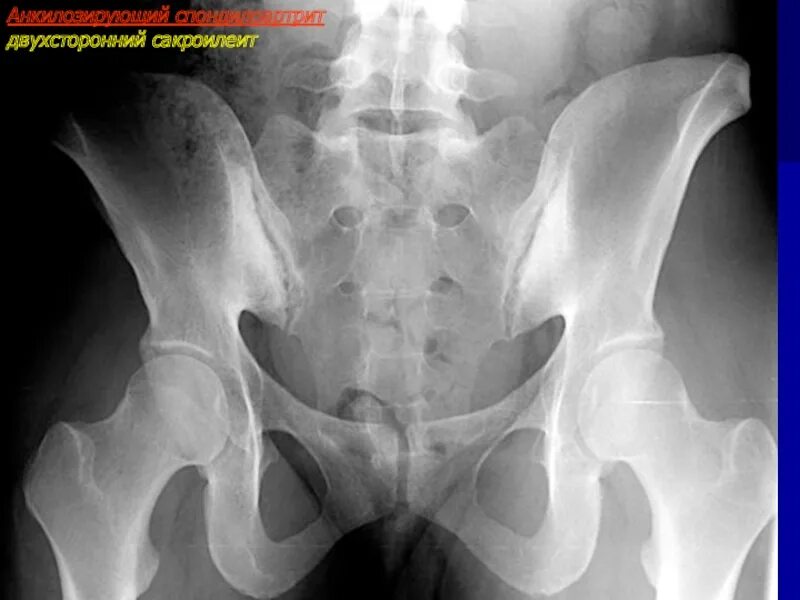

Болезнь бехтерева тазобедренных суставов